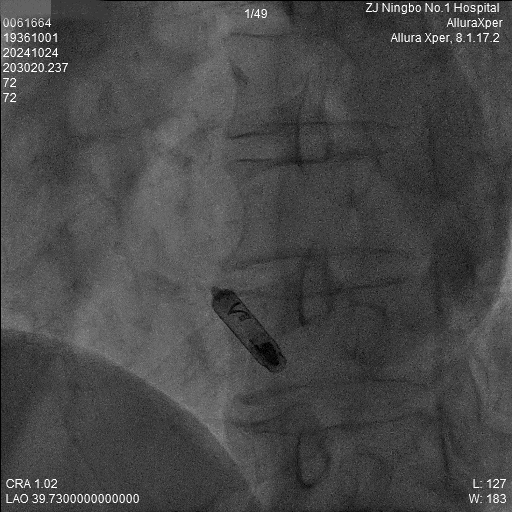

3.调弯进入右室低位间隔后造影,位置理想。左前造影明确贴靠间隔。

a)RAO